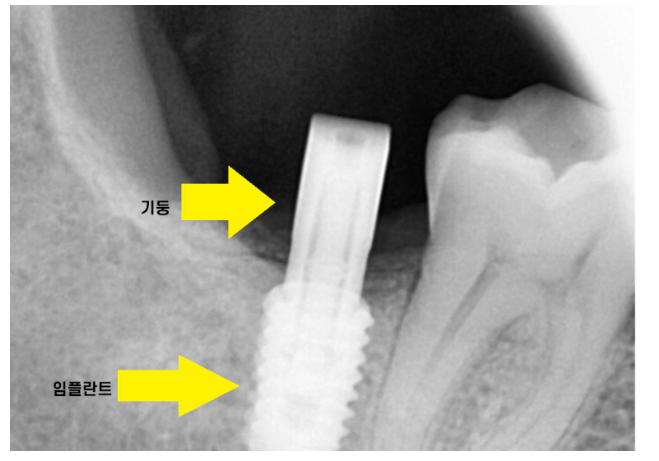

ct를 분석하여

모의 수술을 진행합니다.

임플란트가 들어갈 각도, 사이즈 분석해줍니다!!

여기서 그치지않고 수술 중간에도 원하는 방향에

제대로 심어지고 있는지

한번 더 확인해줍니다.

3번에 걸쳐서 정확도를 높여줍니다.

1)ct를 통해 1차 분석

2)가이드 제작

3)수술 중 중간 분석

그렇기 때문에 잘못된 방향으로 임플란트가

심어질 수가 없습니다.